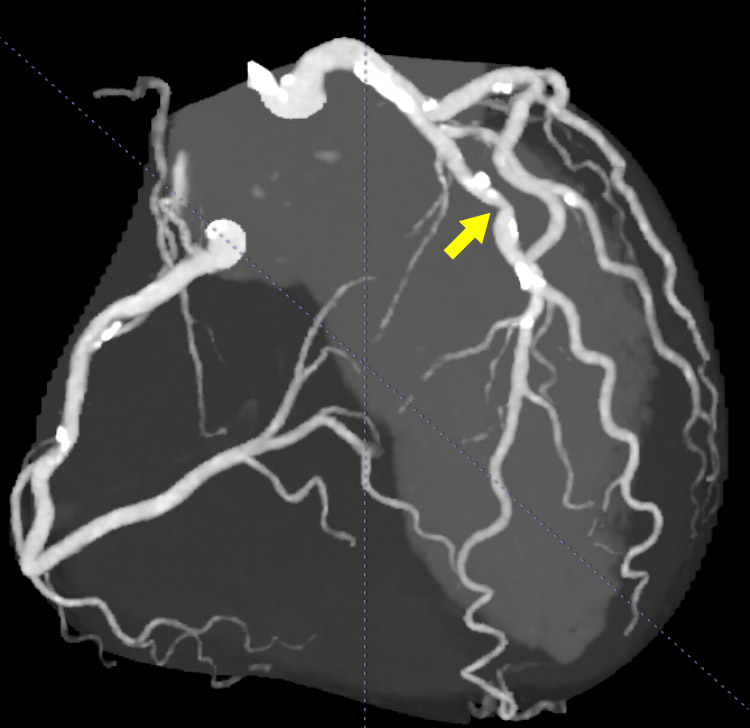

最新の心臓CT・FFRct解析

心臓CTで撮影した画像から冠動脈の3Dモデルを作成し、血流解析(FFRct)を行っています。この解析によって、血流を数値化し、狭心症の診断や治療の必要性を判断することが可能です。

心臓CT

FFRct